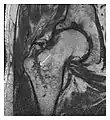

a

b

Figure 13: Partial osseous avulsion of the gluteal muscles at the greater trochanter in a 59-year-old man who presented with the right hip pain without a history of trauma. Lauenstein view and anteroposterior and radiographs (not shown) did not show an obvious fracture line or disruption of bony contours in the acetabulum or the right femoral neck. (a) Coronal T1-weighted MRI displays an incomplete fracture line extending partially from the greater trochanter (arrow). (b) Coronal short tau inversion recovery MRI shows heterogeneous hyperintensity in the same region (arrow) as well as hyperintensity within the gluteus medius and minimus muscles (arrowheads) consistent with tissue edema and hematoma.[1]

Figure 14: Subcapital insufficiency fracture in a 55-year-old man with a left hip pain without a history of trauma. Anteroposterior and Lauenstein view radiographs centered on the left hip do not show an obvious fracture line, but mild acetabular osteophytosis was noted consistent with hip osteoarthritis (not shown). (a) Coronal T1-weighted MRI shows a linear low-signal band through the femoral neck corresponding to a fracture line (arrowheads). (b) Bone scintigraphy shows focal uptake (arrow) corresponding to the fracture.[1]